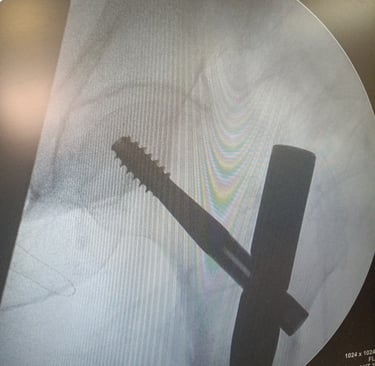

- Tratamento cirúrgico de fraturas ( transtrocanteriana, subtrocanteriana, diafisária de fêmur, acetábulo )